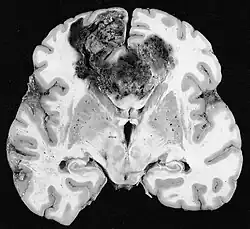

Glioblastome

Die sowohl häufigsten als auch bösartigsten Gliazelltumoren sind Glioblastome. Sie bestehen aus einer heterogenen Masse schlecht differenzierter Astrozytomzellen hauptsächlich bei Erwachsenen. Normalerweise treten sie in den Gehirnhälften auf, seltener am Hirnstamm oder Rückenmark. Außer in sehr seltenen Fällen dehnen sie sich wie alle Hirntumoren nicht über die Strukturen des Zentralnervensystems hinaus aus.[22]

Das Glioblastom kann sich aus einem diffusen (II. Grades) oder einem anaplastischen Astrozytom (III. Grades) entwickeln. In letzterem Fall wird es als sekundär bezeichnet. Tritt es jedoch ohne Vorstadien oder ohne Anzeichen einer früheren Malignität auf, bezeichnet man es als primär. Glioblastome werden mittels Operationen, Bestrahlung und Chemotherapie behandelt. Sie sind schwer zu heilen und es gibt nur wenige Überlebensfälle von über drei Jahren.[23]

Im Tumorgewebe ist im Allgemeinen der größere Anteil der Kontrastverstärkung auf die besondere Blut-Tumor-Schranke zurückzuführen, die den Durchgang von Iod (CT) und Gadolinium (MRT) in den intratumoralen extravaskulären Interstitialraum ermöglicht. Dadurch steigt das Signal (Dichte oder Intensität) des Tumors. Es sollte jedoch darauf geachtet werden, dass die Kontrastverstärkung die Neoplasie von Periwundödemen nicht mit Sicherheit abgrenzt. Tatsächlich zeigt der anatomisch-pathologische Befund bei malignen infiltrierenden Gliomen Tumorgewebe, wie zum Beispiel beim Glioblastom und anaplastischem Astrozytom, auch jenseits des vasogenen Ödems, das durch die Zerstörung der Blut-Hirn-Schranke durch den Tumor verursacht wird. Letzterer klinischer Zustand ist durch diagnostische Bildgebung schlecht nachweisbar.[5][6]

Auf -Kernspintomogrammen erscheint ein intrakranieller Tumor als massive Läsion, die nach Verwendung des Kontrastmittels lumineszierender werden kann. Eine Signalanomalie gibt es jedoch immer in -Kernspintomogrammen, die auf das Vorhandensein einer Neoplasie oder eines vasogenen Ödems hinweist. Normalerweise ist eine stärkere Lumineszenz (Kontrastverstärkung) ein Hinweis auf einen Tumor höheren Malignitätsgrades. Ein Kontrastring ist charakteristisch für ein Glioblastom, wobei der Lumineszenzanteil dem lebenswichtigen Teil des bösartigen Tumors und der dunklere -hypointense Bereich der Gewebenekrose entspricht.[4]